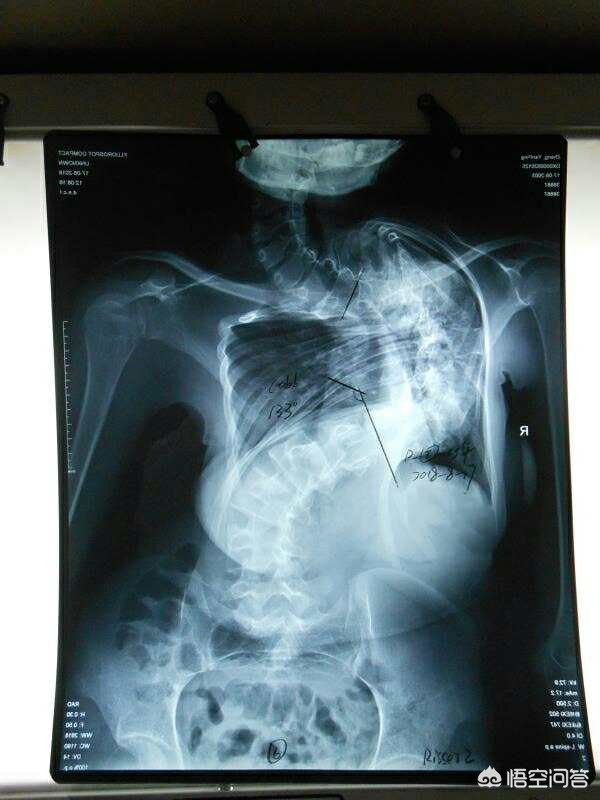

1,结构性脊柱侧弯,就是先天性发育缺陷,出现椎体结构问题,严重的从婴儿时就会出现,随身体生长越来越严,角度有可能在100度以上,身体明显变形扭曲,需要手术结合长期的康复训练调整,减少其它后遗症的发生。

这是比较严重的结构性脊柱侧弯,达到了133度,内脏位置和功能都受到影响。

第二、根据严重程度来分类。分为轻度、中度、重度以及极重度。Cobb角在40度到80度之间为中度的脊柱侧弯,Cobb角大于80度的往往是重度脊柱侧弯。小于40度的轻度脊柱侧弯可以通过保守治疗,例如支具、体育运动锻炼等等。40度到80度之间的中度脊柱侧弯,通过支具是没有太大的效果,有可能会影响到患者的心肺功能,需要考虑手术治疗。